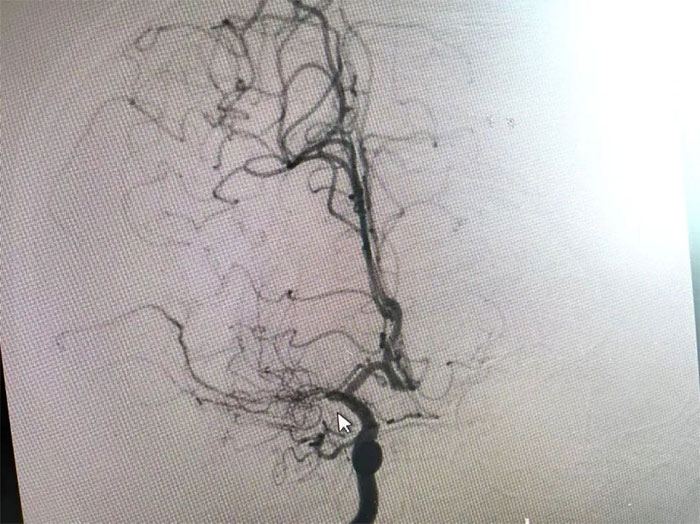

在与患者及家属充分沟通后,李振并主任为周先生展开了DSA(数字减影血管造影)检查。

在检查中发现,周先生右侧大脑中动脉M1段闭塞,可见烟雾状异常血管网生成;左侧大脑中动脉M1段重度狭窄(约70%)。符合烟雾病的典型影像学特征。

▲ 检查发现烟雾状异常血管网

▲右侧大脑中动脉M1段闭塞,左侧重度狭窄

烟雾病又名Moyamoya病,脑底异常血管网,是一组以Willis环双侧主要分支血管(颈内动脉虹吸段及大脑前、中动脉,有时也包括大脑后动脉)起始部慢性进行性狭窄或闭塞,继发出现侧支异常的小血管网为特点的脑血管病。因脑血管造影时,呈现许多密集成堆的小血管影,似吸烟时吐出的烟雾而得名。